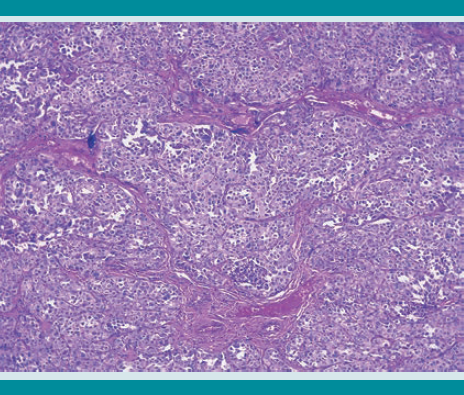

En la glándula tiroides se identificaron dos nódulos: uno en cada lóbulo, de 0.2 cm de diámetro, blanquecinos, de consistencia firme y debidamente circunscritos. Al estudio microscópico correspondieron a neoplasia maligna epitelial constituida por células de tamaño mediano, citoplasma claro o eosinófilo y con discreto pleomorfismo nuclear. Las células estaban dispuestas en grupos separados por una red capilar. En su mayor parte el tumor estaba debidamente limitado por el parénquima tiroideo vecino. La reacción de inmunohistoquímica para sinaptofisina resultó positiva, y con ello se corroboró su naturaleza neuroendocrina. Figuras 1,2,3,4,5,6